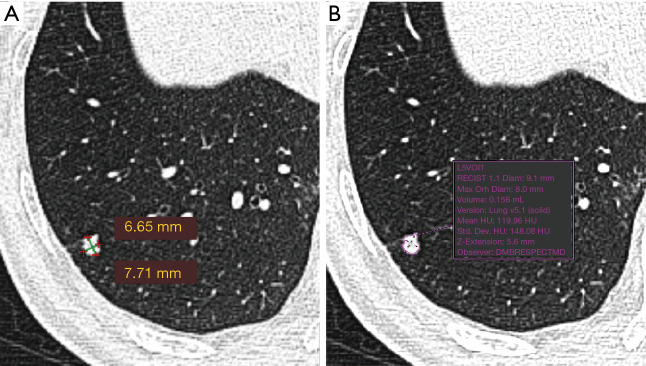

The LDCT images were read first by Chinese radiologists and the visually-detected lung nodules were measured. The detected nodules were measured for a second time by a Dutch radiologist. The first reading was performed by one of the four Chinese resident radiologists (Juxiang Ma, Debei Ma, Zhijun Li and Qingqing Diao) who were specially trained for reading LDCT images for lung cancer screening, and supervised by one of two senior Chinese radiologists (YL and XC) at TJMUCIH. Images were interpreted both at lung and mediastinal window settings. A nodule was registered and measured if the diameter (mean of maximum and perpendicular diameter) ≥4 mm. A nodule was considered part-solid when a non-solid component was visible as well as a solid part in lung window setting (window-width: 1,200 HU, window-level: −500 HU) and the solid part was also visible in mediastinal window setting (window-width: 320 HU, window-level: 35 HU). Measurement was performed in lung window setting. The maximum diameter of a nodule and its perpendicular diameter were measured manually on the axial plane in Carestream Picture Archiving and Communication Systems (PACS) v.11.0 (see the example in Figure 1). The second reading was performed by a radiologist (MDD) in The Netherlands with 10 years of experience in chest imaging, including experience in lung cancer screening at the University Medical Center Groningen, The Netherlands. The measurement of nodules was performed in lung window setting (window-width: 1,200 HU, window-level: −500 HU) in the second reading. The second reader used semi-automated volumetry software (MM Oncology, Syngo.via VB30, Siemens), providing the volume as well as the diameter of lung nodules (see the example in Figure 1). The diameter was registered in three dimensions, including maximum axial diameter, perpendicular diameter and z-axis diameter.

Figure 1.

CT image with manual diameter measurement (A) and semi-automated volume and diameter measurement (B). CT, computed tomography.